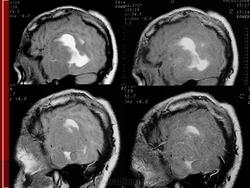

ГМ. Примитивная нейроэктодермальная опухоль (ПНЭО). +

Примитивная нейроэктодермальная опухоль (ПНЭО)